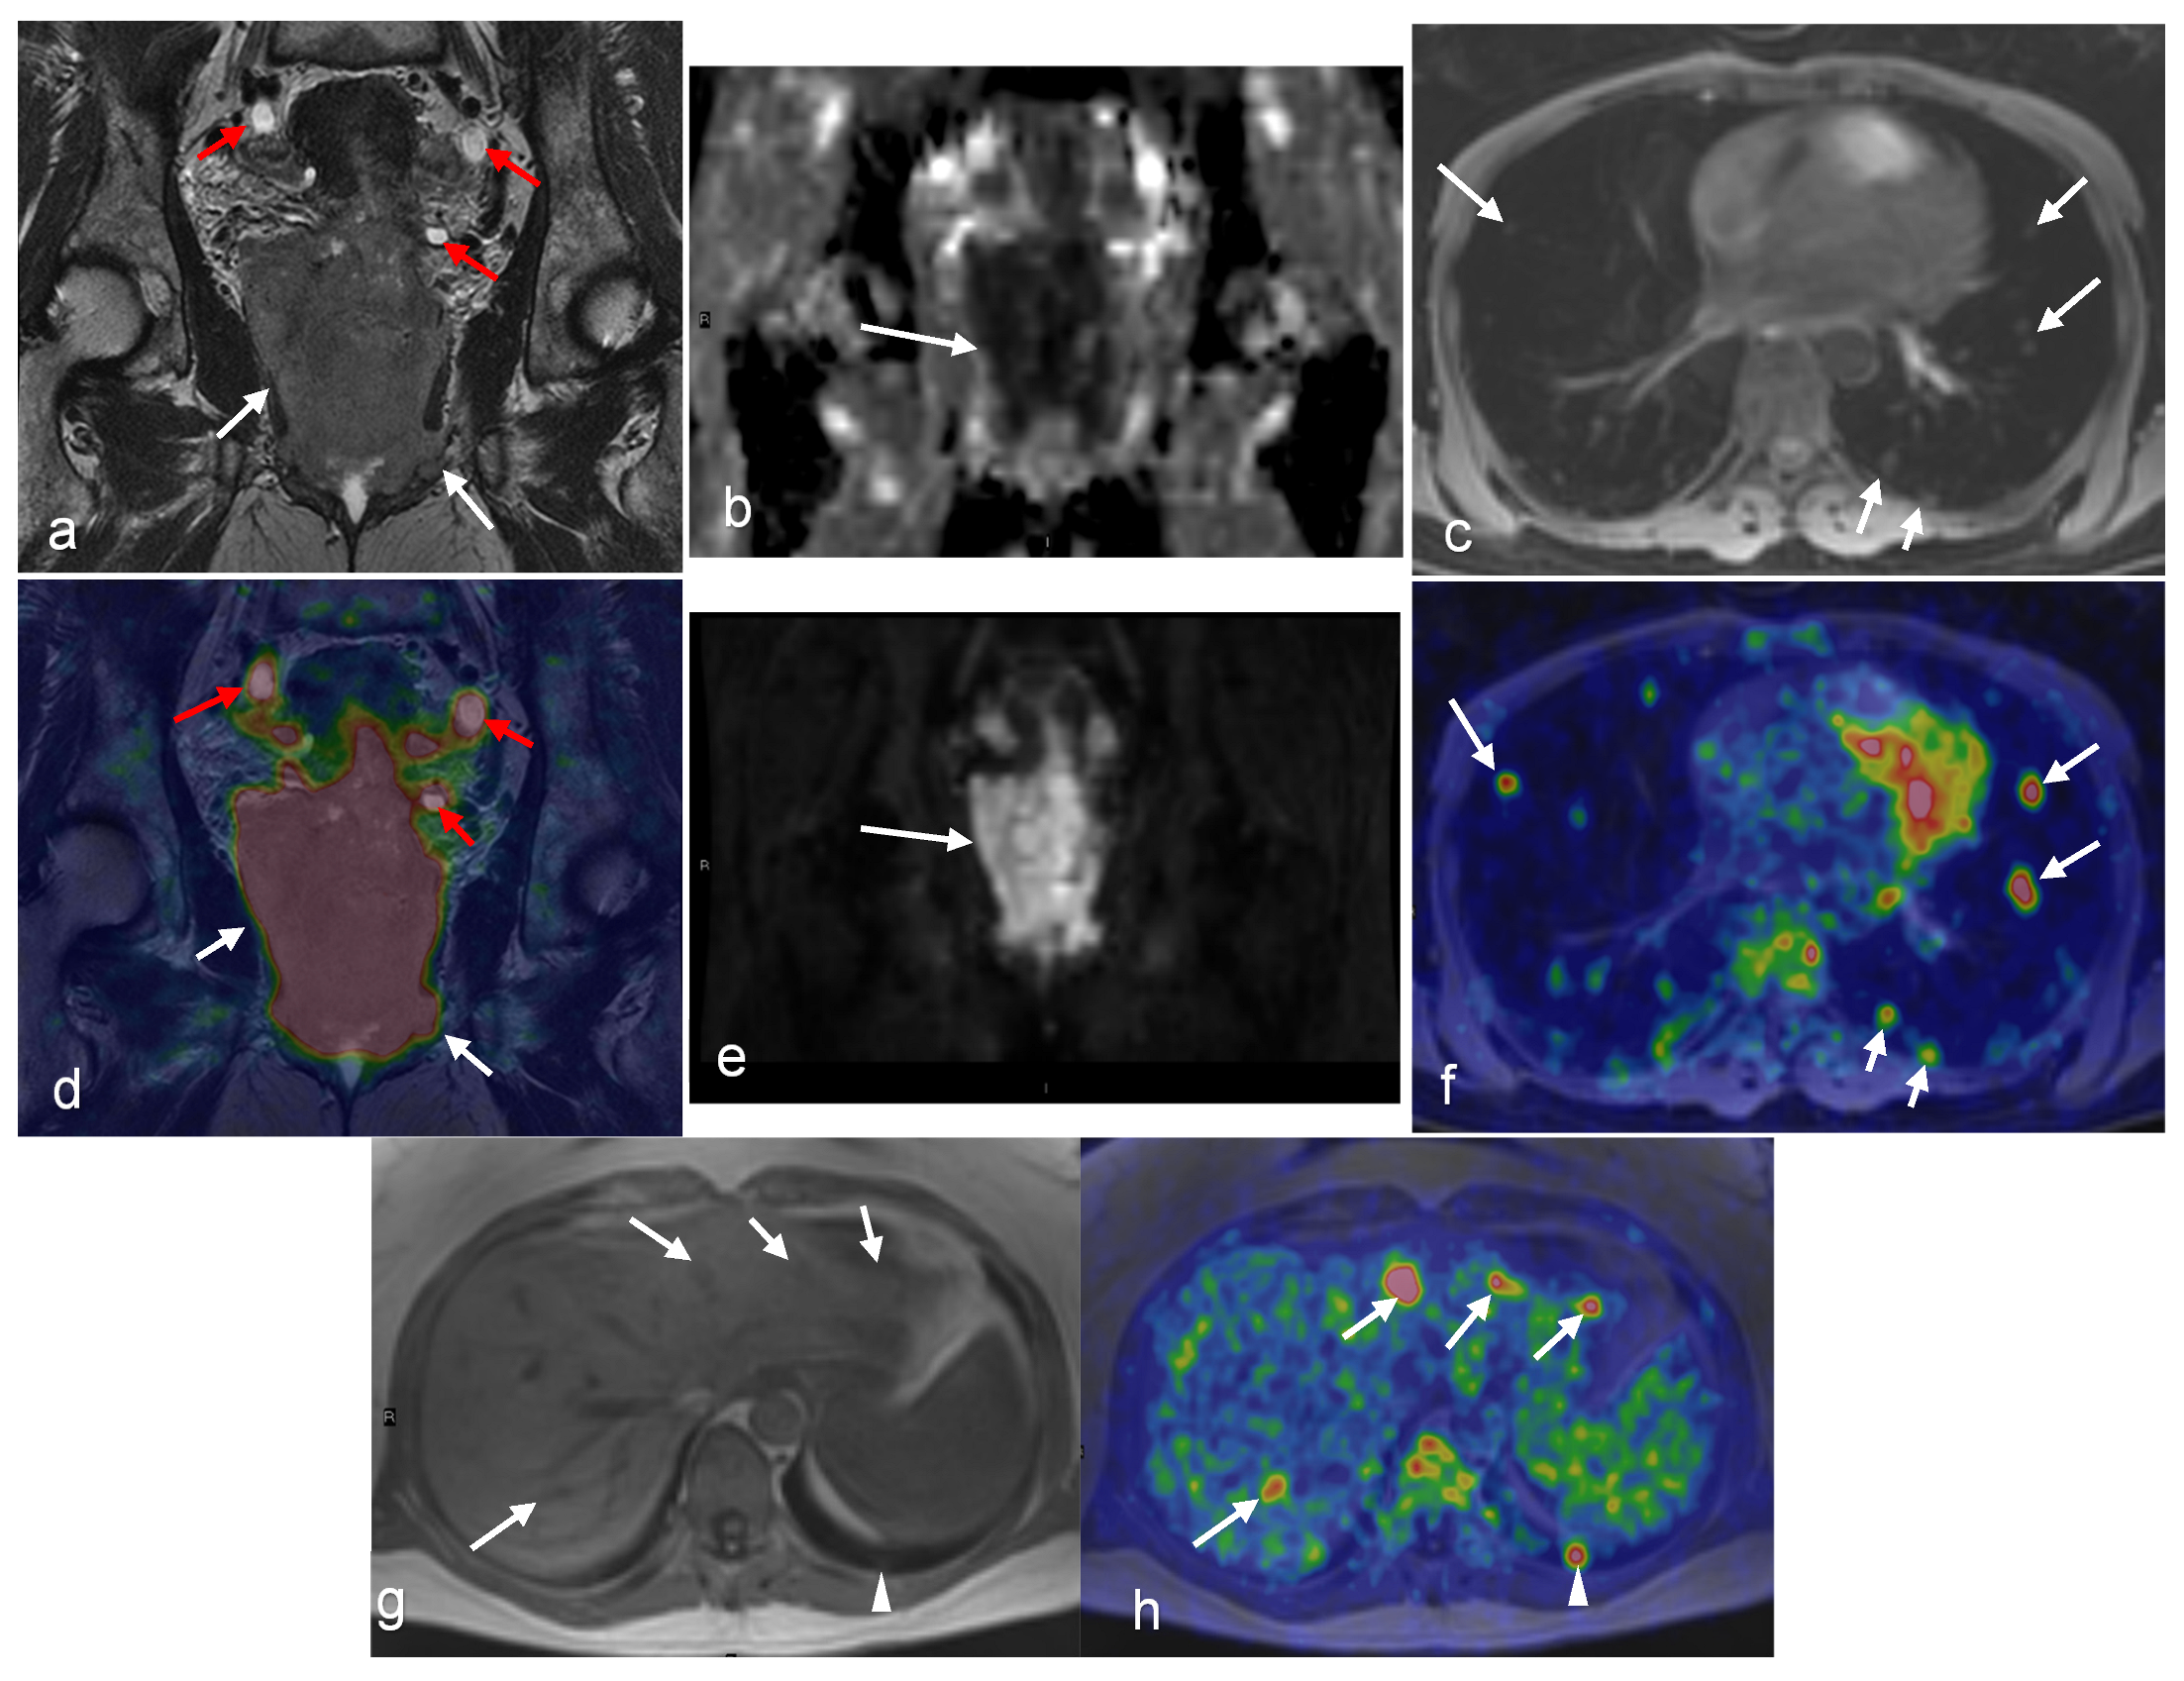

- Grueneisen, J.; Schaarschmidt, B.M.; Heubner, M.; Aktas, B.; Kinner, S.; Forsting, M.; Lauenstein, T.; Ruhlmann, V.; Umutlu, L. Integrated PET/MRI for whole-body staging of patients with primary cervical cancer: Preliminary results. Eur. J. Nucl. Med. Mol. Imaging 2015, 42, 1814–1824. [Google Scholar] [CrossRef] [PubMed]

- Gong, J.; Wang, N.; Bian, L.; Wang, M.; Ye, M.; Wen, N.; Fu, M.; Fan, W.; Meng, Y. Cervical cancer evaluated with integrated 18F-FDG PET/MR. Oncol. Lett. 2019, 18, 1815–1823. [Google Scholar] [CrossRef] [PubMed]

- Steiner, A.; Narva, S.; Rinta-Kiikka, I.; Hietanen, S.; Hynninen, J.; Virtanen, J. Diagnostic efficiency of whole-body 18F-FDG PET/MRI, MRI alone, and SUV and ADC values in staging of primary uterine cervical cancer. Cancer Imaging 2021, 21, 16. [Google Scholar] [CrossRef] [PubMed]